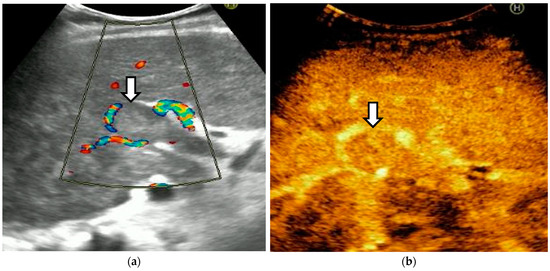

The diagnosis of PVT and PC is made by imaging procedures (transabdominal ultrasound with a Doppler or contrast-enhancing computed tomography scan, magnetic resonance imaging, or angiography in the case of therapeutic intended procedures) [1,3,12,13,14,21,29]. Transabdominal ultrasound is a reliable procedure in 60–100% of cases, with an anechoic aspect in recent cases (requiring Doppler examination or CEUS) and a hypoechoic or hyperechoic aspect in chronic cases [22,29]. Doppler examination may show an anechoic or hypoechoic thrombus and a slower (<15 cm/sec) or absent portal blood flow, and is considered the gold standard (color Doppler) for the diagnosis of PC [1], with a sensitivity and specificity of 95% (Figure 1 and Figure 2) [22]. CEUS can help the diagnosis of benign or malignant PVT, can characterize associated focal liver lesions [30], allows a better characterization of PVT [31], and also permits better detection of PC—Figure 3 and Figure 4 [32]. CT scan and MRI (Figure 5 and Figure 6) are more accurate for the evaluation of liver causes (HCC, abscesses, and other tumors) or other local causes (pancreatitis, diverticulitis, and appendicitis), and for complications (bowel infarction or perforation), and may show permeability of the portal venous system and the flow direction [1,22]. Malignant PVT has intra-thrombus arterial signals on CT, MRI, and/or CEUS, with portal vein diameter frequently 23 mm or above, and with the presence of the tumor at imaging examination (Figure 4 and Figure 6) [21].

Figure 3.

CT scan in a patient with recent surgery for transverse colon adenocarcinoma. (a) The enlarged portal vein, with intraluminal thrombus and peri-gastric collateral circulation, indicated by black arrow. (b) A 59/34 mm portal cavernoma, indicated by black arrow.

Figure 4.

MRI scan in a patient with pancreatic carcinoma. (a) Enlarged portal vein, with intraluminal thrombus. (b) A hilar 5.1/3.3 cm portal cavernoma.

Transabdominal ultrasound with Doppler protocol (Figure 1a,b and Figure 2a,b), CT scan (Figure 3a,b), and MRI (Figure 4a,b) were used for the diagnosis in 88.9, 75.1, and 15% of cases, respectively. CEUS was used for the diagnosis in 49 cases (25.9%) but in only 29 cases was it used for the evaluation of the thrombus, and in two cases for cavernoma diagnosis (Figure 5a,b and Figure 6a,b).